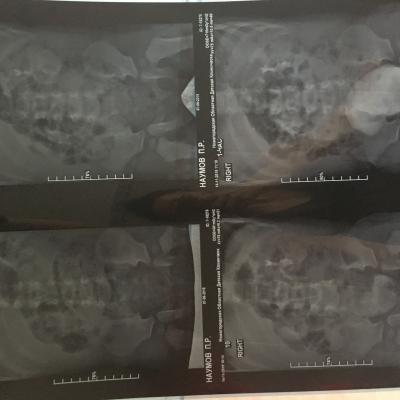

Здравствуйте , с Рождения поставлен диагноз уретерогидронефроз , пмр4 ст. Пол года назад сделали операцию по Коэну, но улучшений нет , рефлюкс стал 3 ст, а функция почки снижена . Лечащий хирург сказал, что ничего предпринимать не нужно, только наблюдение и высокая вероятность сморщивание почки и в последствии ее удаление. Скажите пожалуйста действительно ли уже не спасти почку ?!

Прилагаю снимки до операции и после операции.